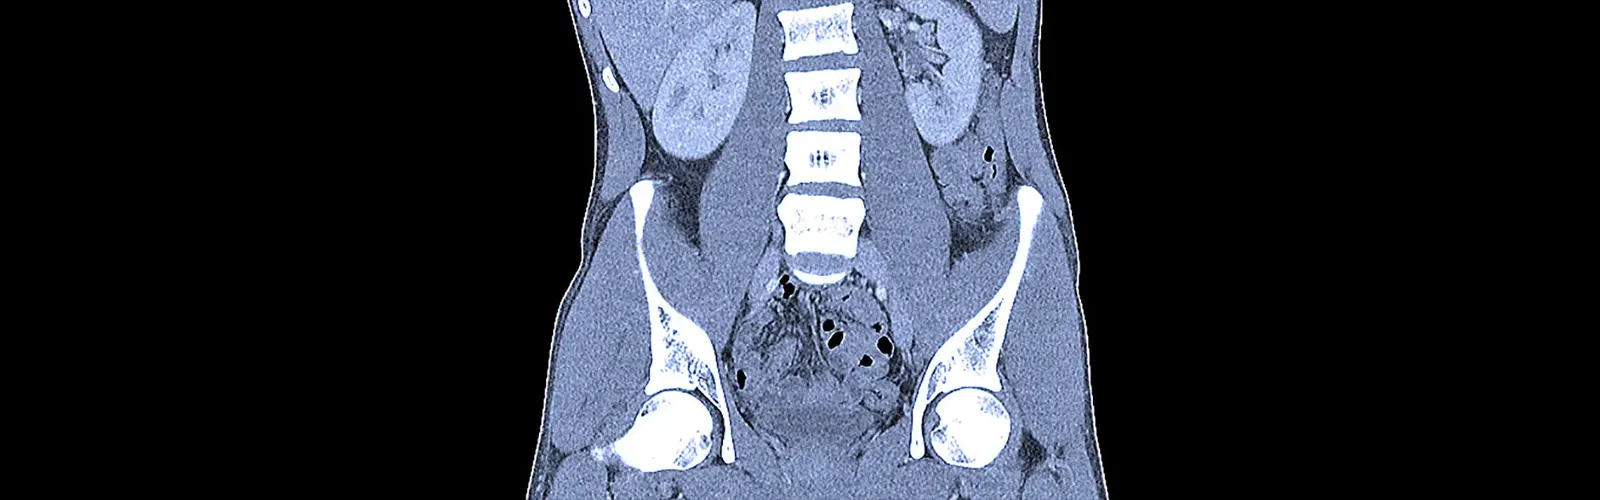

An iodinated contrast medium is frequently utilized while doing a contrast-enhanced computed tomography (CECT) of the abdomen. Iodine is a radiopaque chemical that is present in iodinated contrast agents.

An iodinated contrast medium is frequently utilized while doing a contrast-enhanced computed tomography (CECT) of the abdomen. Iodine is a radiopaque chemical that is present in iodinated contrast agents. This enables improved imaging and diagnosis by absorbing X-rays and improving the visibility of blood arteries, organs, and other structures during the CT scan.